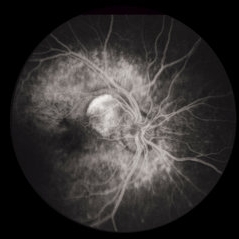

Toxocara Granuloma

Toxocara Granuloma

Feb 25 2013 by Henry J. Kaplan, MD

Toxocara granuloma of optic nerve; F/A.

Condition/keywords: ocular toxoplasmosis, toxocara granuloma, toxocariasis